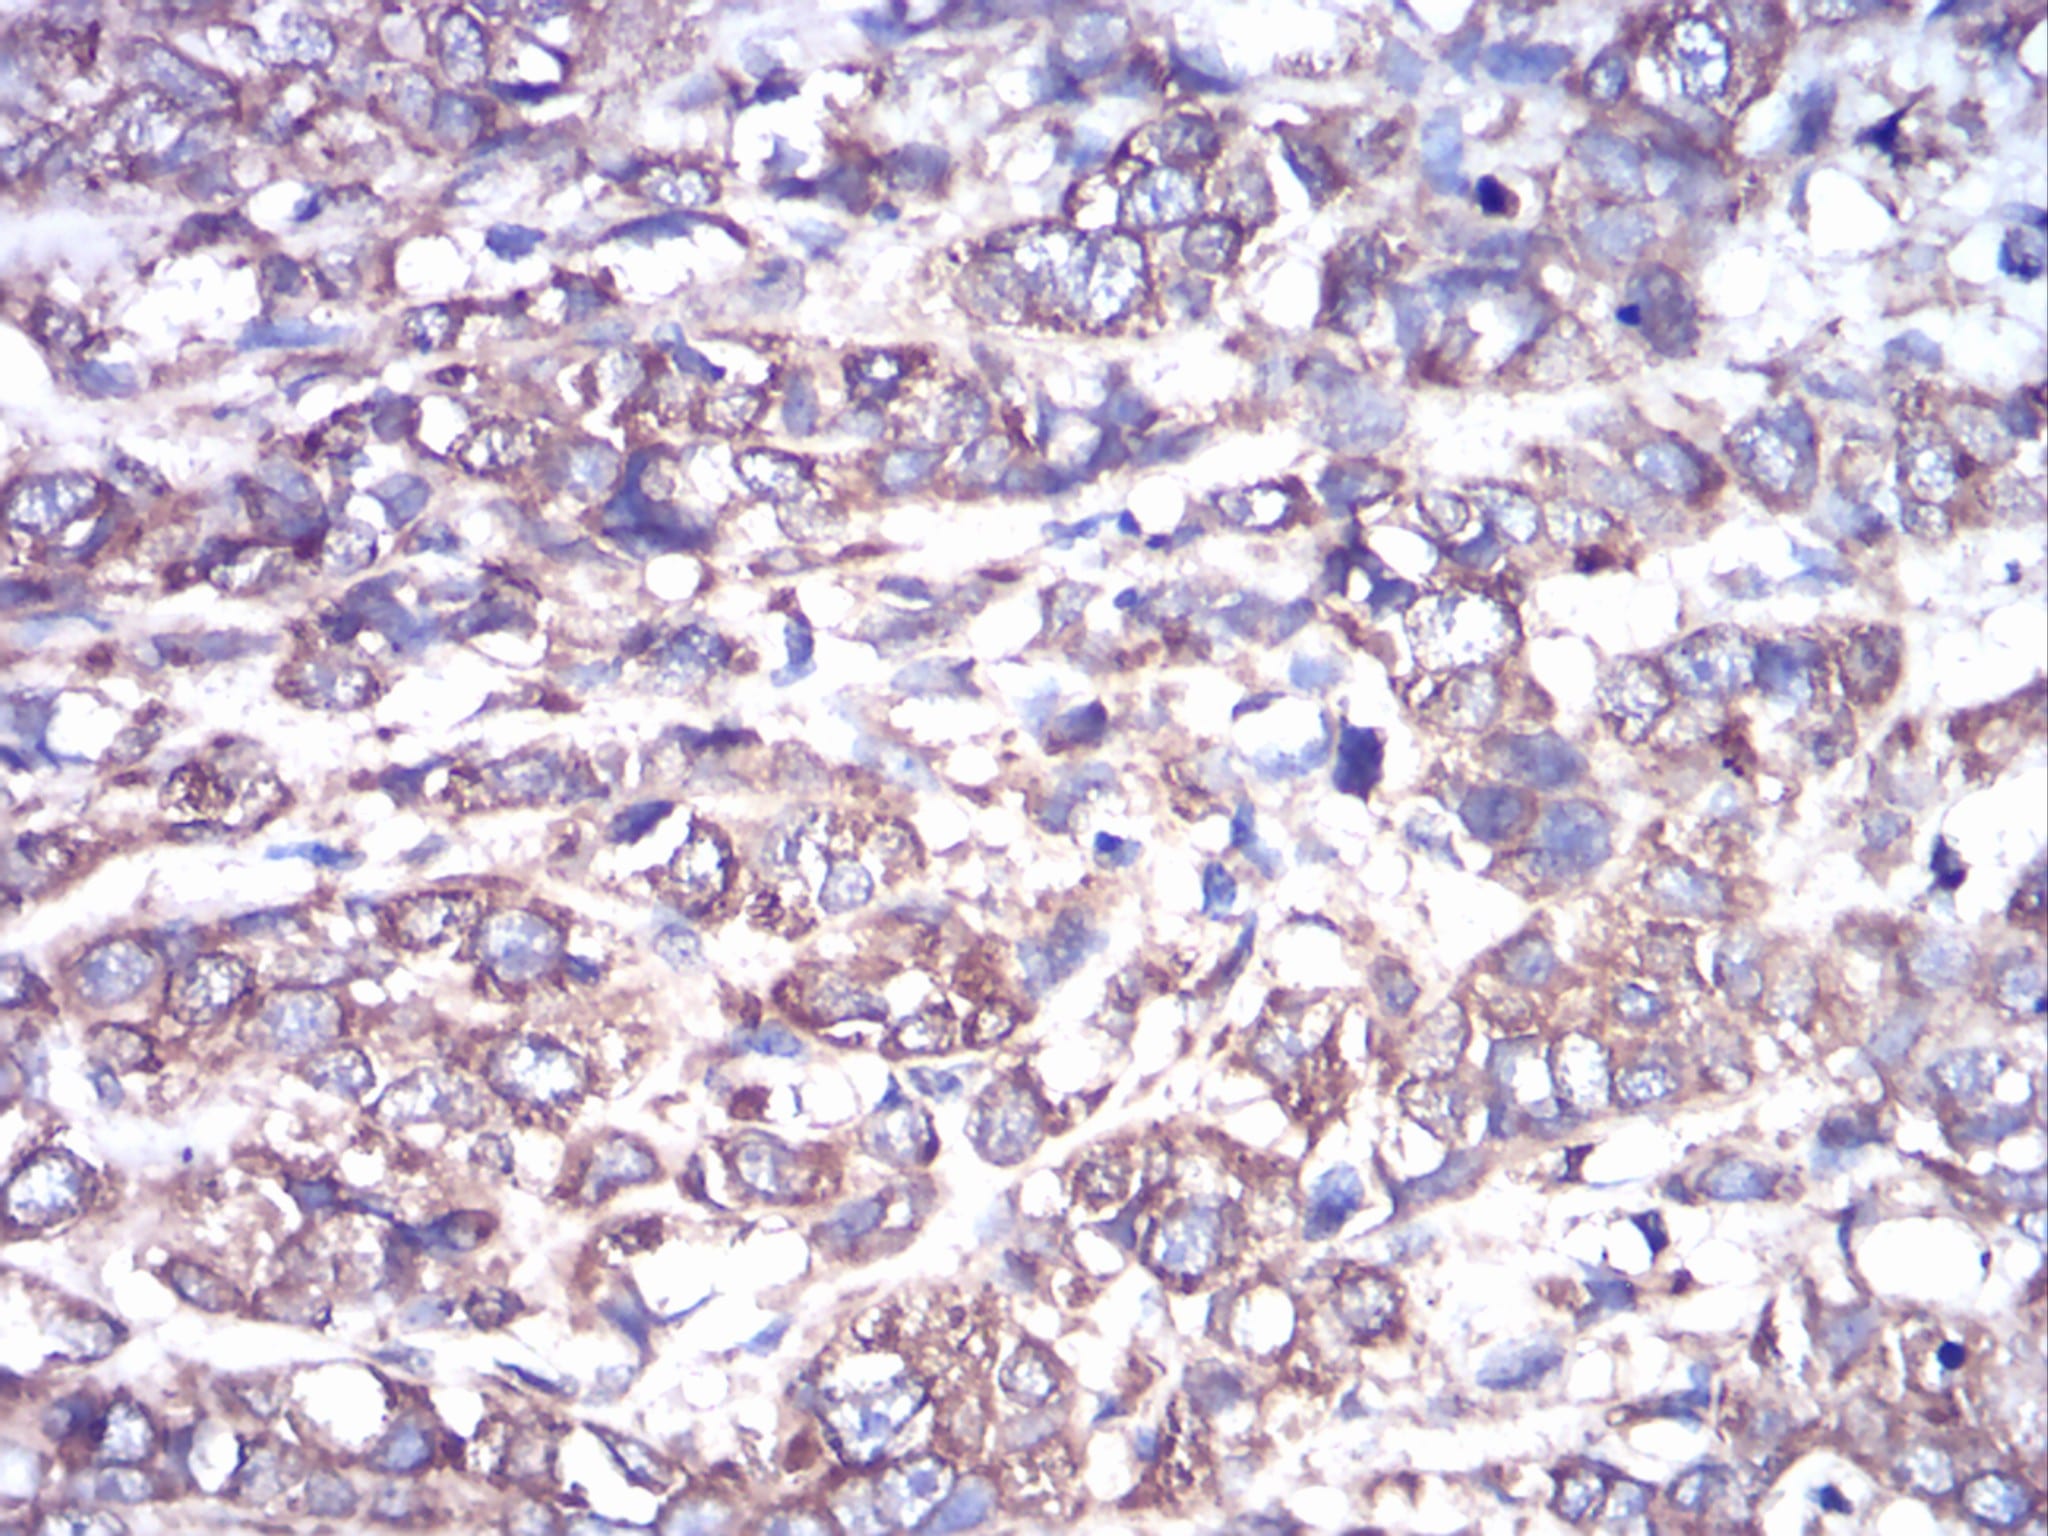

IHC 1/200 - 1/1000 Human,Mouse,Rat